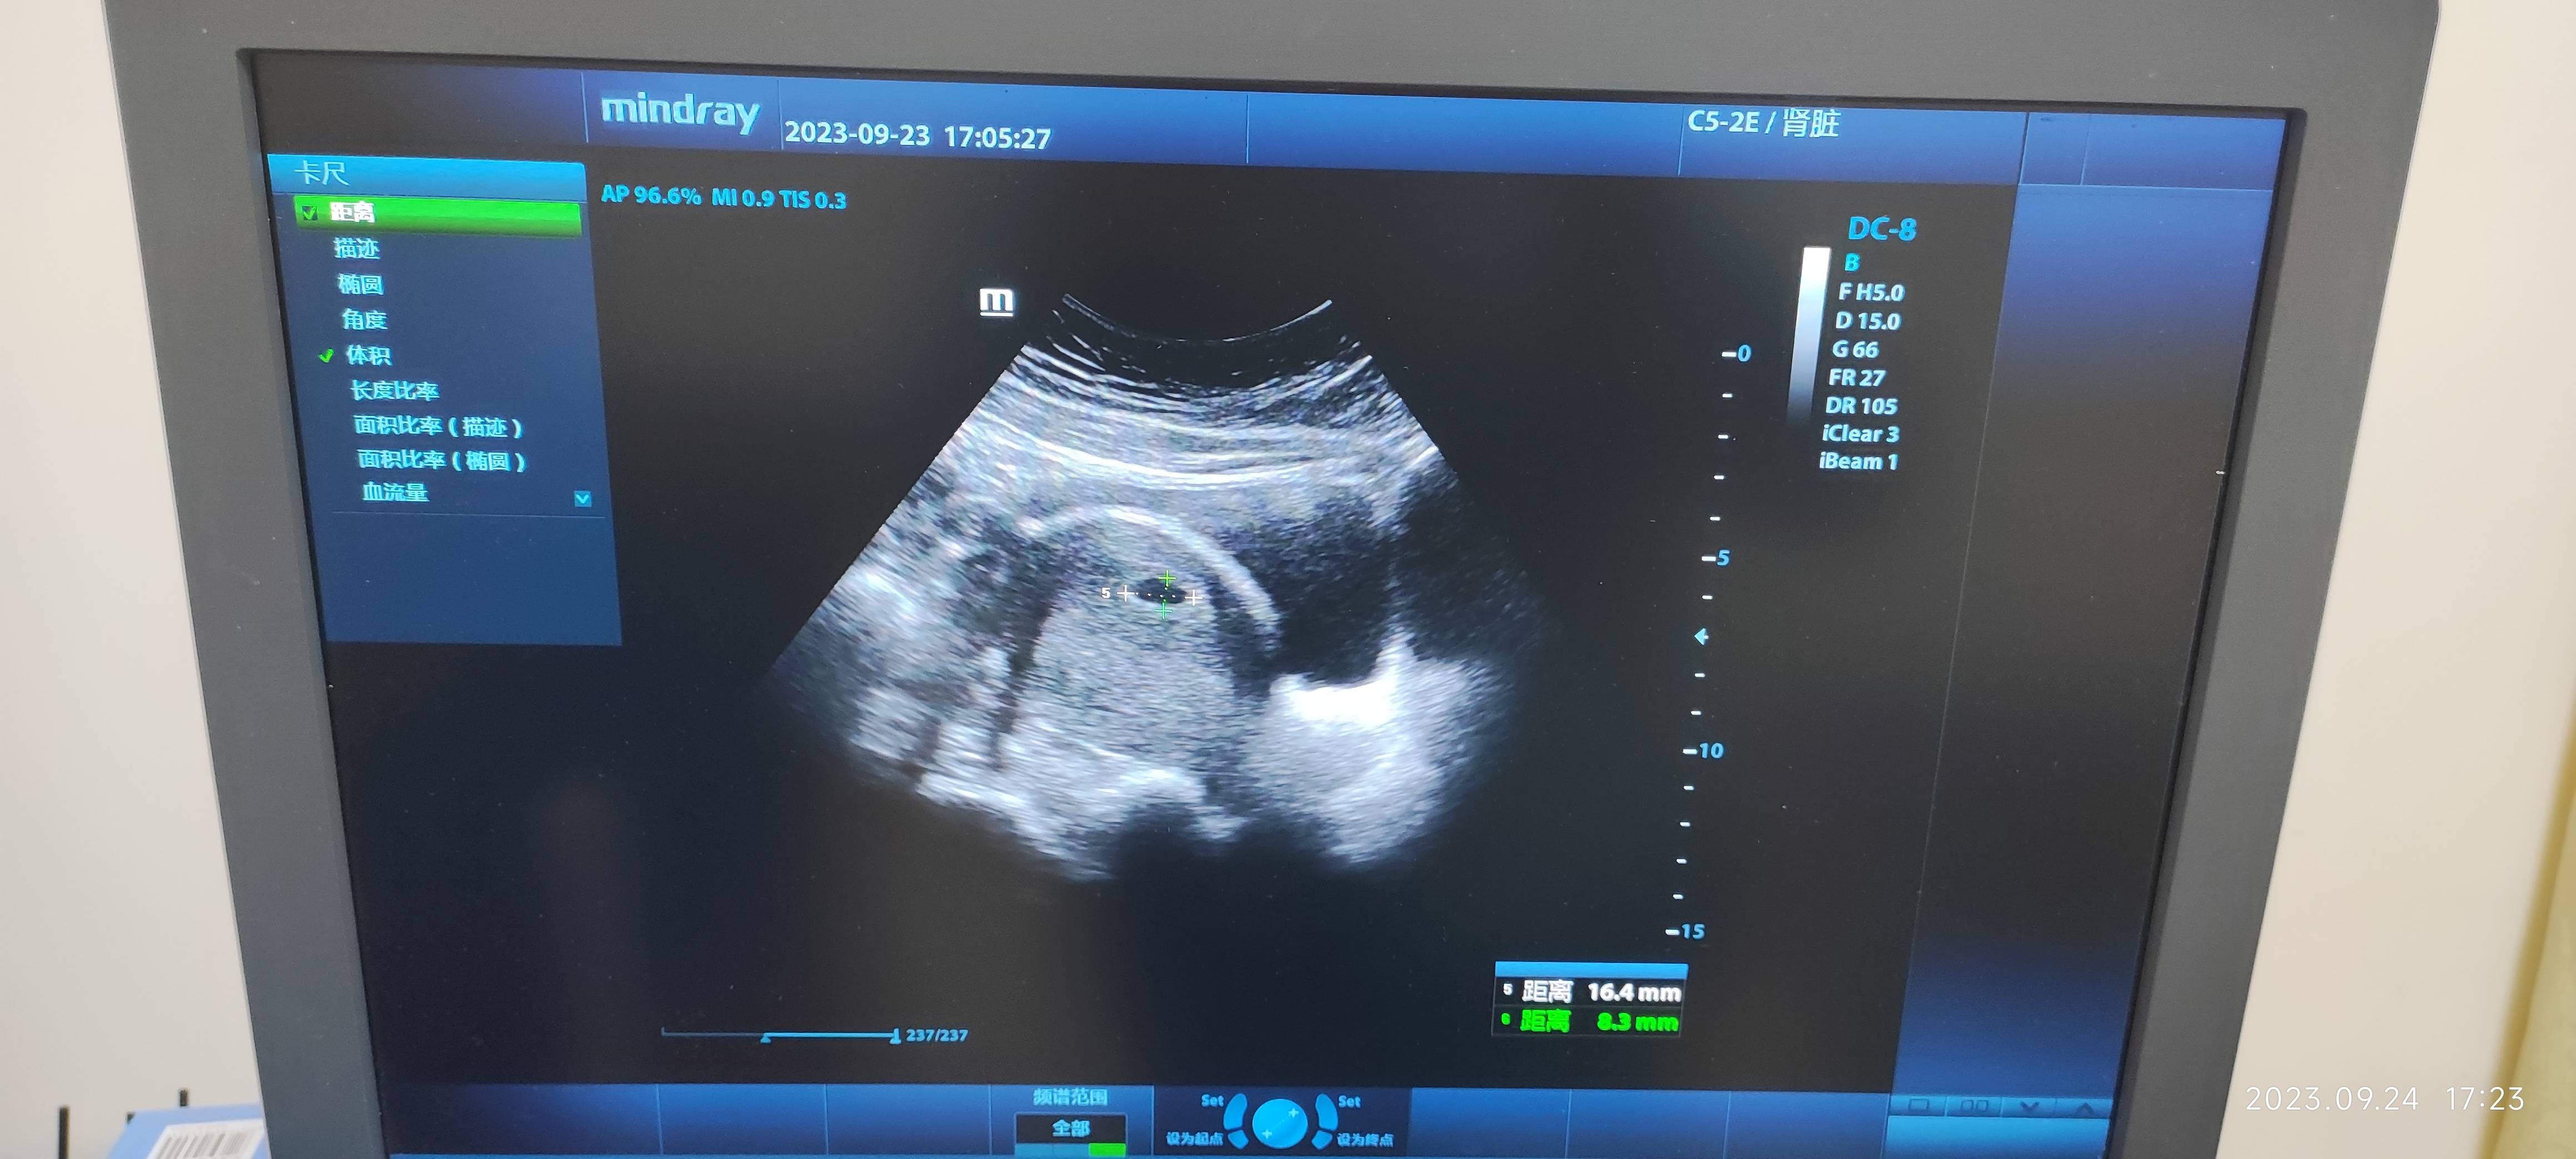

你好,你的图像看不清具体的数值。根据你测血时间你可能要看翻倍情况。如果没有特殊不适,比如流血腹痛这些症状可以不测翻倍情况,翻倍代表胚胎发育可,不翻倍也不一定胚胎不好,要结合自身症状还有既往是否有不良孕产史综合判断。祝好

如果是一家单位检查,这个HCG数值下降了,有胚胎发育不良可能,如果不是一家单位检查,可以9—27在后一家医院再检查一次,宫腔看到孕囊,一周复查有没有胎芽胎心。

你好,您所发的这个图片看的不是太清楚,建议您可以把图片分开发,或者是使用文字把您所检查的具体数值和医生的超声描述。再详细的描述一下。